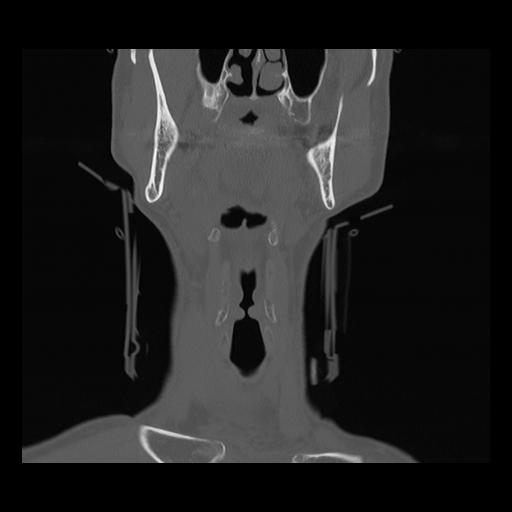

16 HUESO,,Coronal,2.000,HUESO,Coronal,